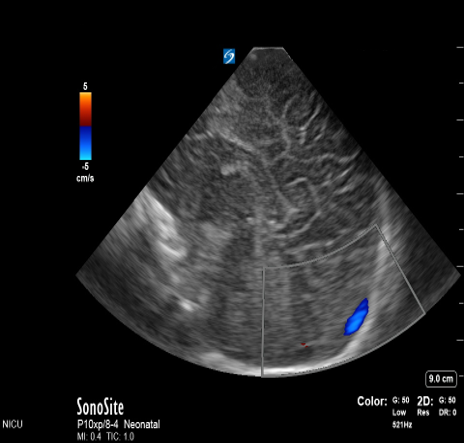

Neonatology Transverse Sinuses 1 Image